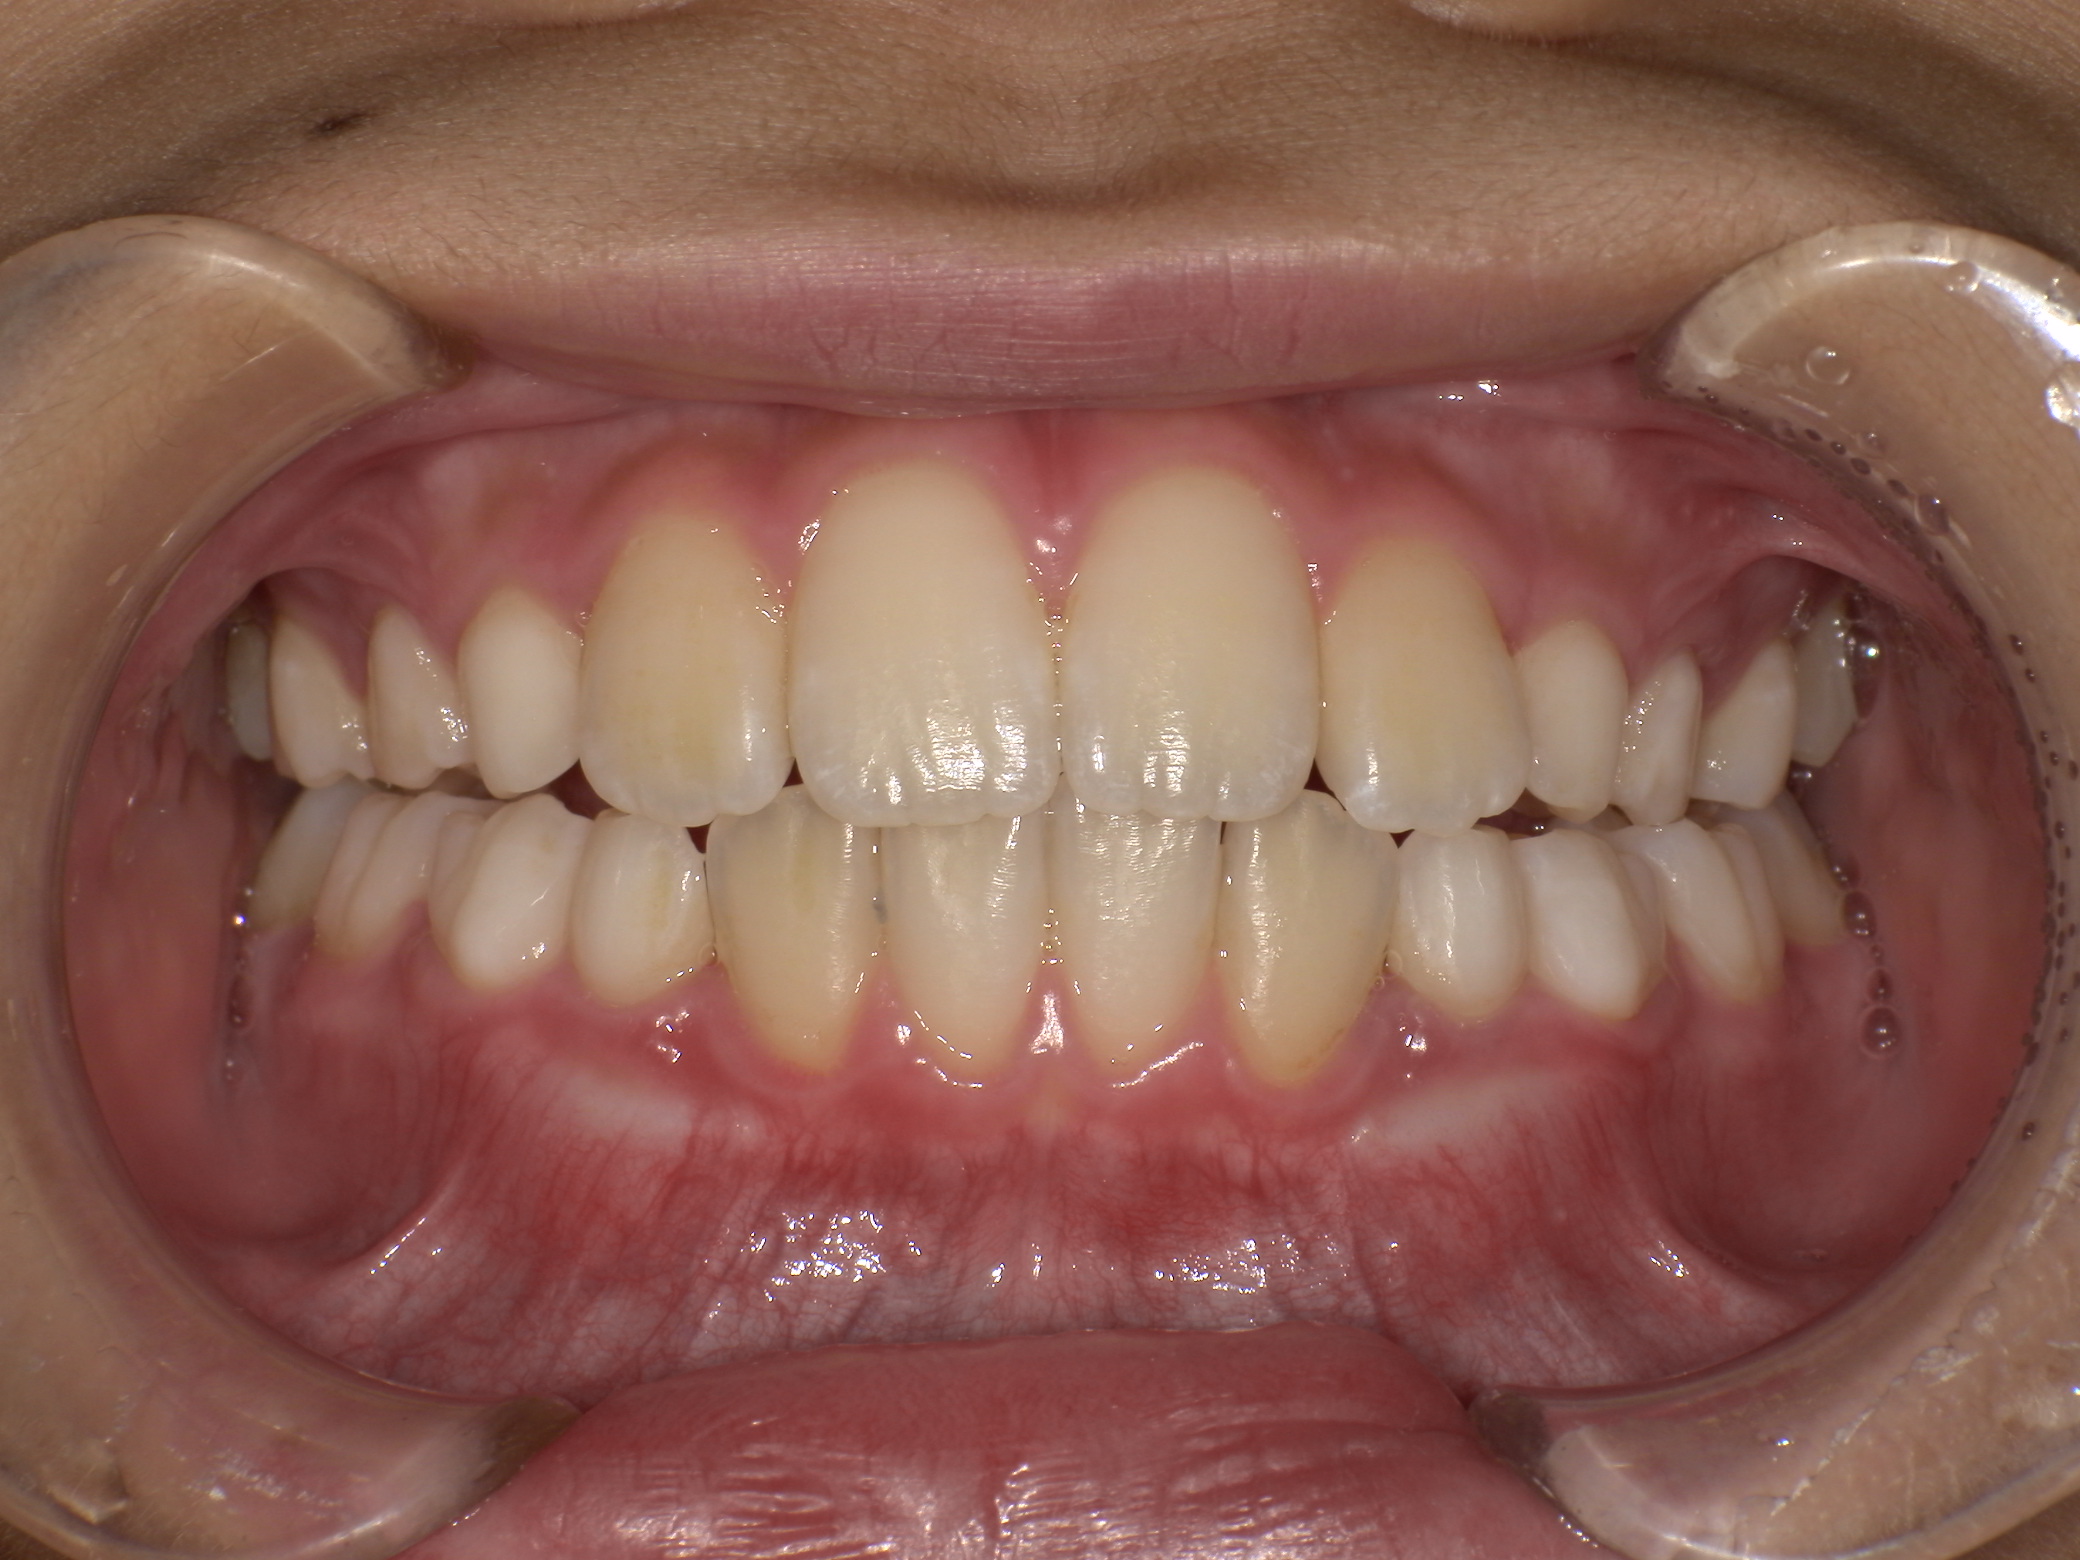

バイオネーターの症例

主訴 | 上の前歯が気になる |

---|---|

治療内容 | バイオネーター |

治療期間 | 1年 |

治療費用 | 330,000円(税込) |